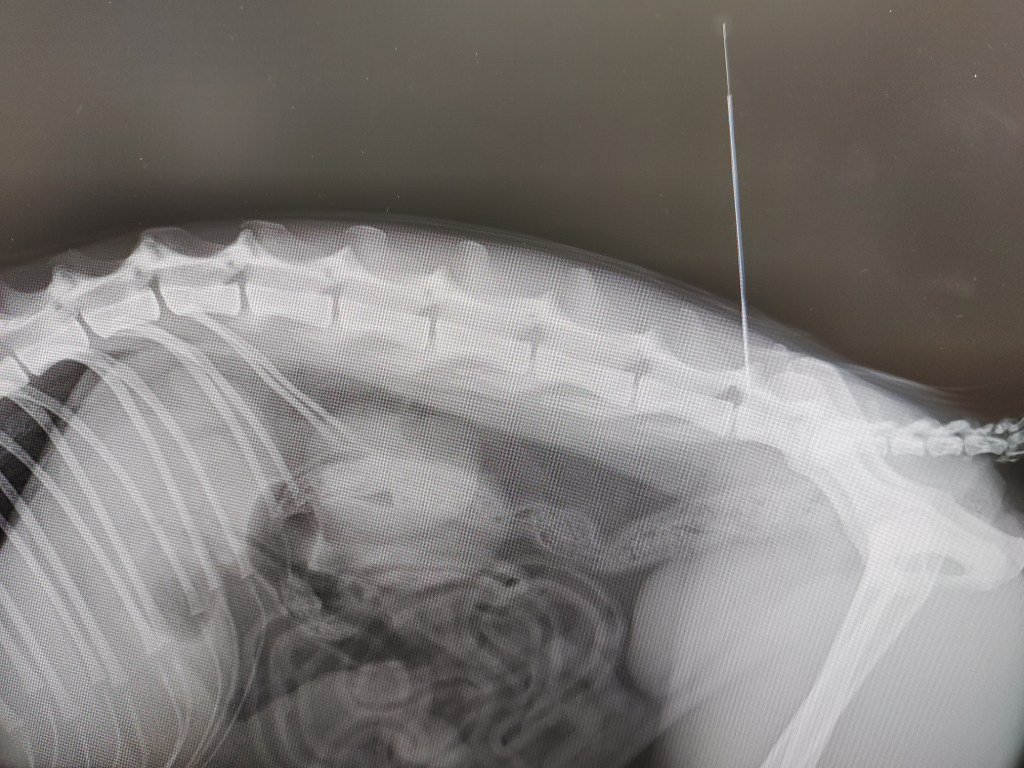

環椎軸椎不安定症。これだけだと正直レントゲンとその他のシグナルメントだけで手術に踏み切っても良い気がします。が、後頭骨形成不全の手術も同時にすべきか評価してからの方が無難かもしれません。思考回路停止型のリハビリ通院はあんまり好きではないです。